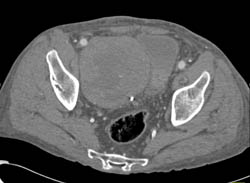

Recurrent Renal Cell Carcinoma in Left Renal Bed